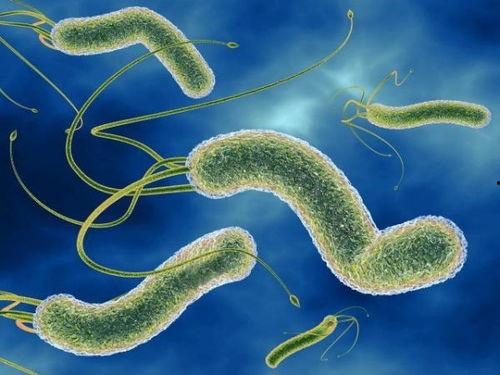

幽门螺旋杆菌:潜伏在胃里的“小怪兽”

首先,得先认识一下这位“小怪兽”。幽门螺旋杆菌,顾名思义,是一种螺旋形的细菌,它喜欢在胃里安家。据统计,全球约有50%的人感染了这种细菌,而我国感染率更是高达60%以上。别小看了这个小小的细菌,它可是胃炎、胃溃疡、胃癌等疾病的罪魁祸首。